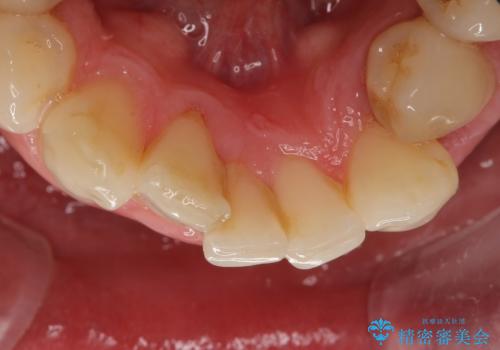

矯正治療とホワイトニングを提案しましたが希望されず、「接客関係の仕事で矯正治療は考えられない、短期間で治療を終わらせたい、ホワイトニングでは難しい位の人工的な白さにしたい」とのご要望により、治療前にワックスアップ模型を作製し何度もコンサルテーションを重ね、治療方針を決定しました。

歯頚ラインが変えられないことや天然歯を削るリスクをご理解頂いた上で、オールセラミッククラウンによる補綴治療を行いました。(見えない奥歯のみ天然歯のままとしました)

下の前歯1本だけ歯軸を変えるために神経をとり根管治療を行っております。

それ以外の歯は神経をとらずに済むよう、慎重かつ丁寧に歯の形態を整えました。